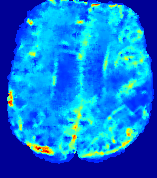

Slice #1Slice #2Slice #3Slice #4Slice #5Slice #6Dgtsuperscript𝐷gtD^{\text{gt}}Refer to captionRefer to captionRefer to captionRefer to captionRefer to captionRefer to caption(a)Refer to captionRefer to captionRefer to captionRefer to captionRefer to captionRefer to caption(b)Refer to captionRefer to captionRefer to captionRefer to captionRefer to captionRefer to caption(c)Refer to captionRefer to captionRefer to captionRefer to captionRefer to captionRefer to caption(d)Refer to captionRefer to captionRefer to captionRefer to captionRefer to captionRefer to caption(e)Refer to captionRefer to captionRefer to captionRefer to captionRefer to captionRefer to caption(f)Refer to captionRefer to captionRefer to captionRefer to captionRefer to captionRefer to captionRefer to caption000.060.060.060.120.120.120.180.180.180.240.240.240.300.300.30(mm2/s)𝑚superscript𝑚2𝑠(mm^{2}/s)

Figure 13: PIANO effectiveness and robustness testing: diffusion imaging via diffusion. Top row shows Dgtsuperscript𝐷gtD^{\text{gt}} used for simulating the ground truth pure diffusion. (a)-(f) refer to the results for D𝐷D estimated from the ground truth pure diffusion image time-series where Rician noise at levels 0%, 2%, 4%, 6%, 8%, 10% was added respectively.

Similarly, starting from the same initial condition C0superscript𝐶0C^{0} as in the ‘Advection Imaging’ experiment for each patient, we simulate concentration time-series {Cti(Ω)|i=0, 1,, 40}conditional-setsuperscript𝐶subscript𝑡𝑖Ω𝑖0140\{C^{t_{i}}\in\mathbb{R}(\Omega)|i=0,\,1,\,\ldots,\,40\} via a diffusion PDE, where we define the ground truth diffusivity D:=Dgtassign𝐷superscript𝐷gtD:=D^{\text{gt}} via the ADC map of the ISLES 2017 training set (ADC values are scaled by 0.000010.000010.00001 to ensure numerical stability):

Note this is likely not a spatially representative ground-truth for perfusion imaging, as it measures different effects from diffusion imaging. However, we still use it as a quasi-realistic pattern of diffusivity in the brain. We also added 2%, 4%, 6%, 8%, 10% levels of Rician noise to obtain simulations of ‘Diffusion Imaging’. The estimated Destsuperscript𝐷estD^{\text{est}} given concentrations of all noise levels for one patient are shown in Fig. 13, PIANO estimation results for all patients are summarized in Fig. 11 (b). Again, PIANO demonstrates its capability to recover the underlying diffusion field. In Fig. 13, when the noise level is increasing, some noisy patterns indeed appear in the associated Destsuperscript𝐷estD^{\text{est}}. Note that the ground truth diffusivity applied in this simulation experiment is about ten times larger than the diffusivity estimated in reality (Fig. 3, Fig. 4).